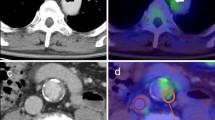

Imaging protocols for 18FDG-PET-CT have been described in detail in previous publications [12]. 18FDG-PET-CT scans were performed using a Siemens Biograph mCT scanner. Subjects fasted for at least 6 h prior to infusion of 200 MBq of 18F-FDG (5.5 mCi). Before PET scanning, a low-dose CT was performed for the attenuation of correction, anatomic coregistration, and fusion of PET-CT images (multiple times). The maximum standard uptake values (SUV) of 18F-FDG were measured in an axial orientation along each carotid artery from 1 cm up to 3 cm below the bifurcation, which was performed by manually drawing the circular regions of interest that encompassed the vessel wall. The target-to-background ratio (TBR) was calculated from the ratio of the maximal arterial standardized uptake values and mean venous background activity within the superior vena cava (correction for aorta) and the jugular vein (correction for carotids). After the 18F-FDG infusion, the PET images of the subjects were collected every 10 min until the 18F-FDG uptake levels entered the plateau stage [13] (Fig. 1).

Characteristics of 18F-FDG uptake in atherosclerotic plaques

Significant 18F-FDG uptake was shown in atherosclerotic plaques, as evidenced by the local concentration of 18F-FDG in the vascular wall of the diseased segments. These plaques showed different 18F-FDG uptake levels, with the highest uptake levels reaching 3.0, while the lowest levels reached only 1.4. In addition, significant differences in the 18F-FDG uptake velocity were also found, with 24 subjects reaching peak values in only 15 min (group A), 32 subjects in 25 min (group B), 28 subjects in 35 min (group C), 48 subjects in 45 min (group D), and, in the slowest group, 24 subjects in 55 min (group E). Furthermore, there was no correlation between the 18F-FDG uptake levels and 18F-FDG uptake velocity in any subjects (r = 0.103, p = 0.637).